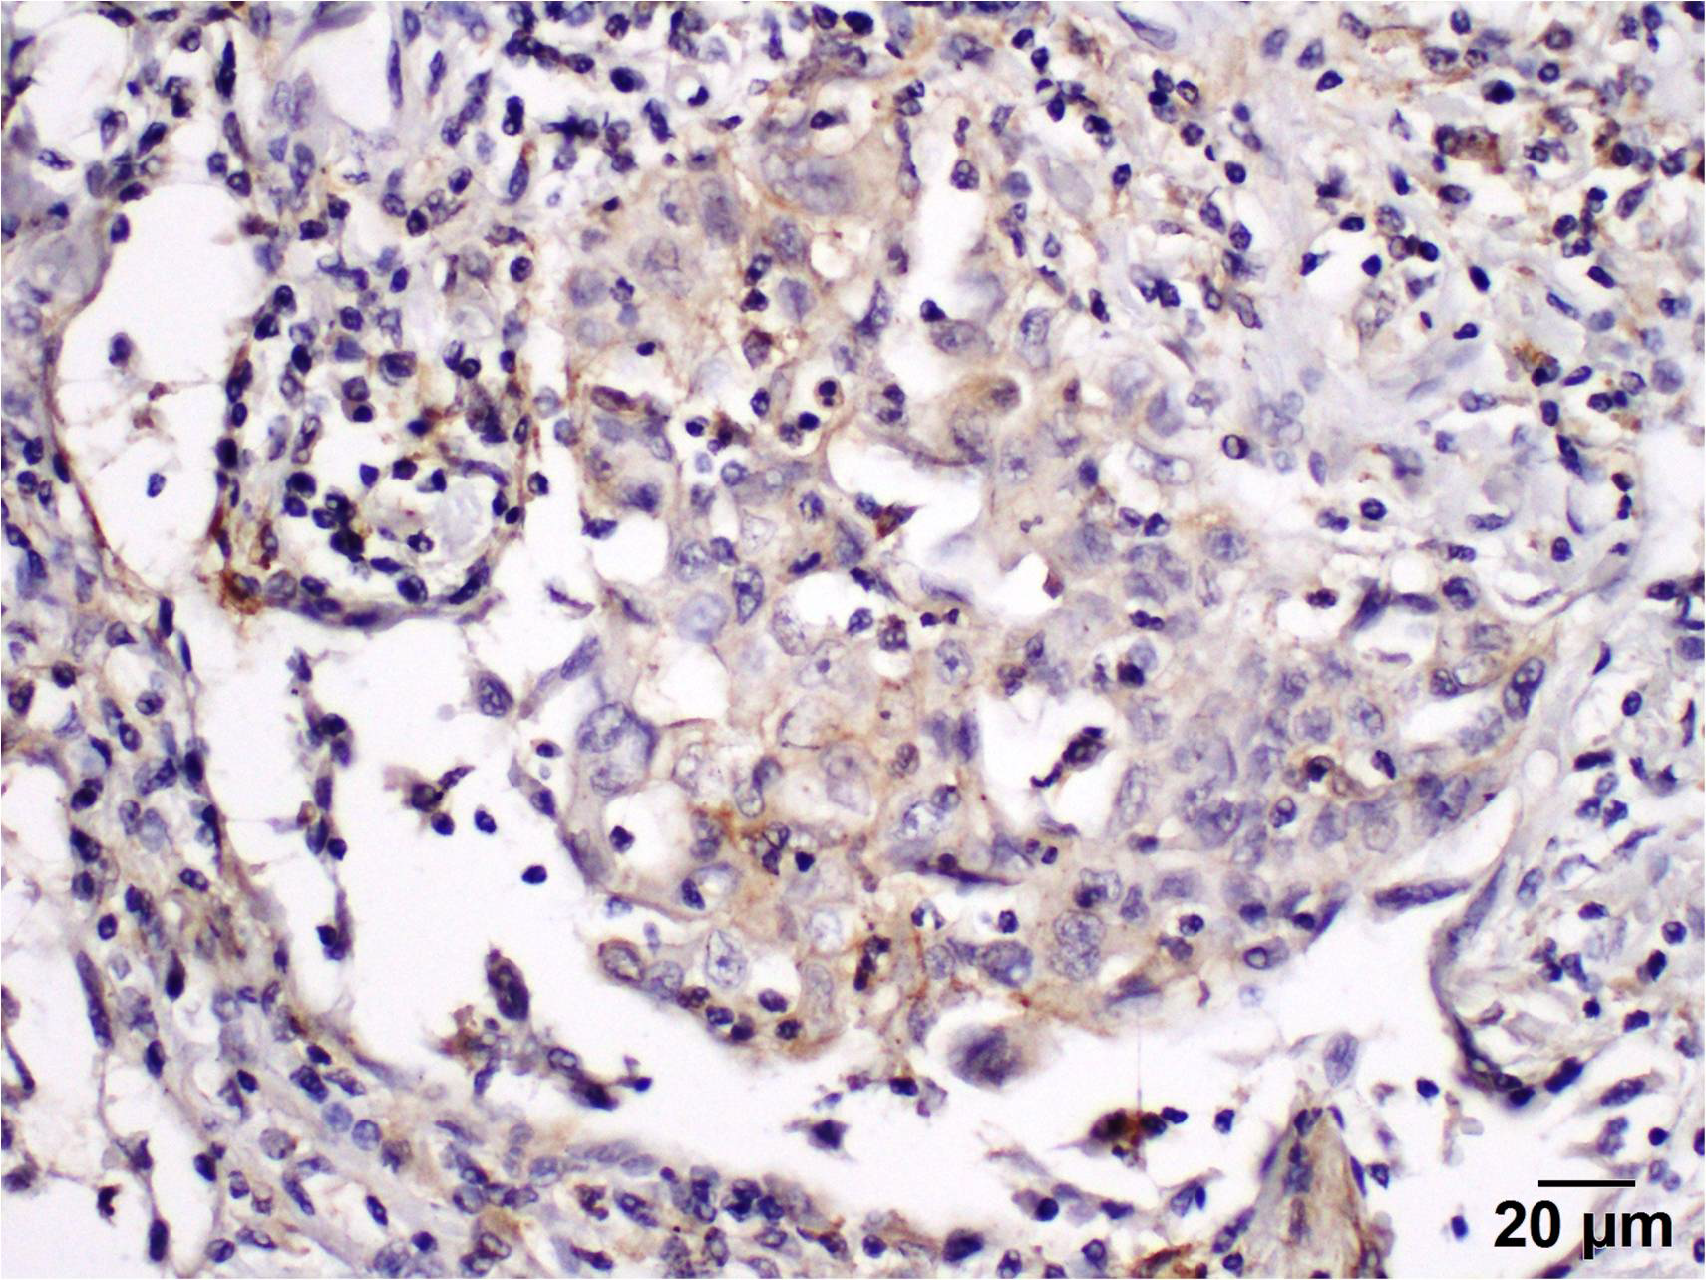

2.4. Immunohistochemistry

2.5. To Evaluate the Level of PD-L1 Expression in the Stroma, the Percentage of Positively